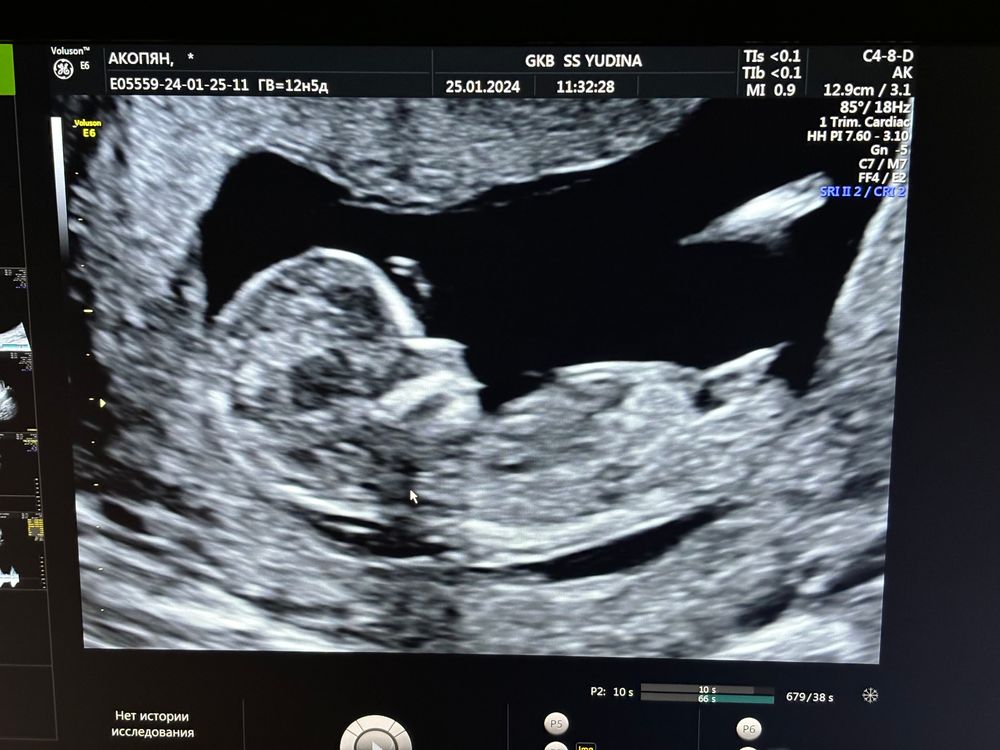

Сходила сегодня на Первый скрининг очень переживала , но малышка хорошо растет соответствует своему сроку , отклонений не каких нет прекреплена по задней стенке матки , сердечко 164 ударов в минуту , и сказали что предположительно будет девочка , очень обрадовалась так как предчувствие было да и хотели дочку проводила скрининг в род доме Юдина и врач сказал больше похоже на половые губки что на мальчишеского нет намека ))) ну что доченька ждем тебя всей большой нашей семьей ❤️❤️ расти и набирайся сил